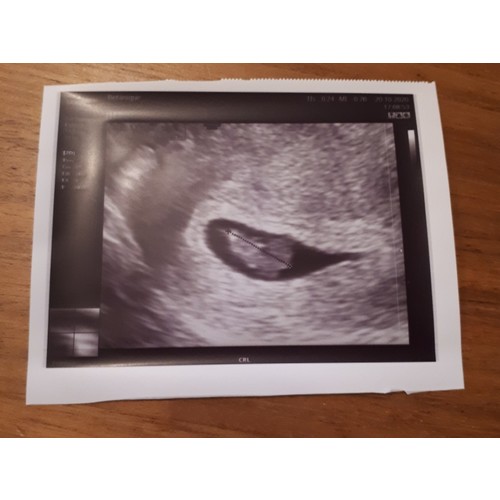

Pff dat is heel naar om mee te maken! Ik snap dat je het nu extra spannend vindt. Dit was onze echo met 7 weken. Links de dooierzak en rechts de baby.